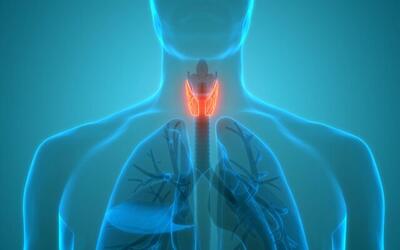

۳ روز قبل / سایت خط سلامت / سلامت / دوران بارداری / کاهش هوش کودک